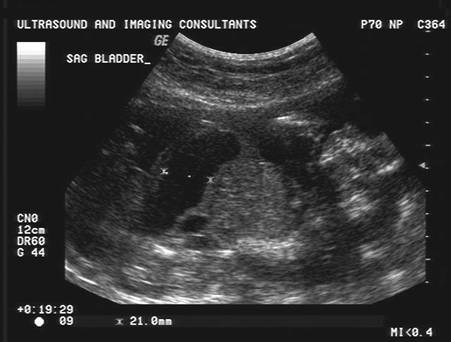

- Enlarged bladder (which

does not appear to change during the scan suggesting urethral

obstruction).

- Urethral obstruction /

atresia (2).

- Megacystis.